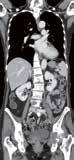

Fall 1:

Biphasische Abdomen-CT bei einer deutlich adipösen Patientin. Hier lässt sich sowohl Dosis sparen als auch die Qualität der Rekonstruktionen verbessern. Beispielsweise findet sich deutlich weniger Bildrauschen, insbesondere im Bereich der parenchymatösen

Portalvenöse Abdomen-CT. Auch hier ist die Dosis am Aquilion Prime SP mit AiCE geringer, zudem auch hier geringeres Bildrauschen mit sehr guter Abgrenzbarkeit, beispielsweise von Leberläsionen.

Abb. 1 a: biphasische Abdomen-CT, Canon Aquilion Prime, Rekonstruktion: AIDR 3D; DLP 1003,6 mGy × cm / 18,1 mSv. Abb. 2 a: biphasische Abdomen-CT, Canon Aquilion Prime, Rekonstruktion: AIDR 3D; DLP 1003,6 mGy × cm / 18,1 mSv. Abb. 1 b: biphasische Abdomen-CT, Canon Aquilion Prime, Rekonstruktion: AiCE; DLP 716,5 mGy × cm / 12,9 mSv. Abb. 2 b: biphasische Abdomen-CT, Canon Aquilion Prime, Rekonstruktion: AiCE; DLP 716,5 mGy × cm / 12,9 mSv. Oberbauchorgane.